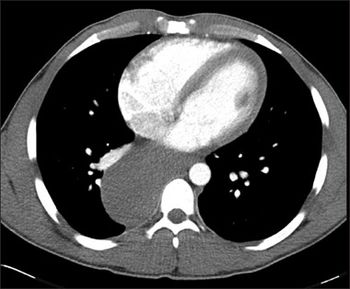

What study would you order to determine the cause of progressively worsening crampy abdominal pain and unintentional weight loss in an older patient with diabetes?

The clinical presentation-crampy abdominal pain after meals, weight loss, and loose stools-is consistent with chronic mesenteric ischemia given this patient's history of diabetes.